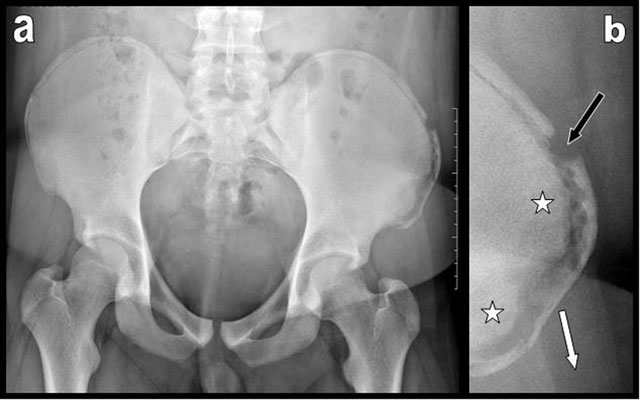

Figure 1

Pelvic plain film (a) and focused view (b) of the left iliac crest illustrate avulsion of the anterior part of the left iliac crest apophysis. Diastasis between the parent bone and the apophysis is clearly visible. The apophysis is displaced outwardly and downwardly (white arrow). Transverse fracture of the iliac crest apophysis itself is associated (black arrow). Preexisting bony sclerosis of the parent iliac bone due to chronic overuse is visible (white stars).